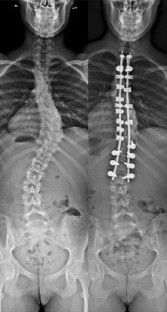

Reciprocal sagittal alignment changes after posterior fusion in the setting of adolescent idiopathic scoliosis

Surgical adolescent idiopathic scoliosis (AIS) management can be associated with loss of thoracic kyphosis and a secondary loss of lumbar lordosis leading to iatrogenic flatback. Such conditions are associated with poorer clinical outcomes during adulthood. The aim of this study was to evaluate sagittal plane reciprocal changes after posterior spinal fusion in the setting of AIS.

Thirty consecutive adolescents (mean age 14.6 years) with AIS Lenke 1, 2 or 3 were included in this retrospective study with 2 year follow-up. Full-spine standing coronal and lateral radiographs were obtained preoperatively, at 3 and 24 months postoperatively. Coronal Cobb angle, thoracic kyphosis (TK) and lumbar lordosis (LL) were measured. Surgical procedure was similar in all the cases, with use of pedicular screws between T11 and the lowest instrumented vertebra (≥L2), sublaminar hooks applied in compression at the upper thoracic level and sub-laminar bands and clamps in the concavity of the deformity. Statistical analysis was done using t test and Pearson correlation coefficient.

Between preoperative and last follow-up evaluations a significant reduction of Cobb angle was observed (53.6° vs. 17.2°, p < 0.001). A significant improvement of the instrumented thoracic kyphosis, TK (19.7° vs. 26.2°, p < 0.005) was noted, without difference between 3 and 24 months postoperatively. An improvement in lumbar lordosis, LL (43.9° vs. 47.3°, p = 0.009) was also noted but occurred after the third postoperative month. A significant correlation was found between TK correction and improvement of LL (R = 0.382, p = 0.037), without correlation between these reciprocal changes and the amount of coronal correction.

Results from this study reveal that sagittal reciprocal changes occur after posterior fusion when TK is restored. These changes are visible after 3 months postoperatively, corresponding to a progressive adaptation of patient posture to the surgically induced alignment. These changes are not correlated with coronal plane correction of the deformity. In the setting of AIS, TK restoration is a critical goal and permits favorable postural adaptation. Further studies will include pelvic parameters and clinical scores in order to evaluate the impact of the noted reciprocal changes.